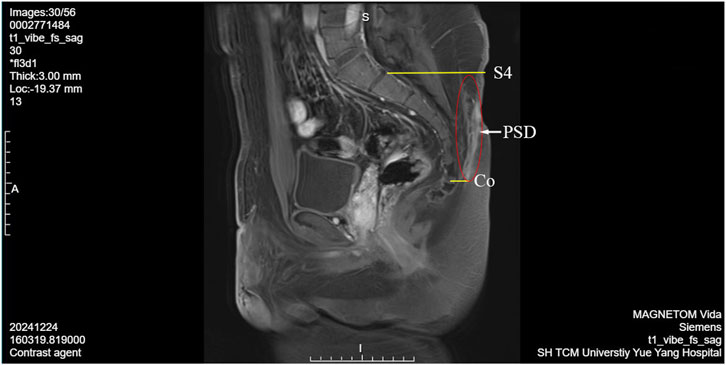

The patient underwent enhanced sacrococcygeal MRI and hydrography. Radiological manifestations: An irregular and abnormal lesion was found in the subcutaneous region of sacrococcygeal region (about the level of sacral vertebra 4 to coccygeal vertebra 1), while went from posterior upward slanting to anterior downward. The wall of the sinus tract showed low signal intensity on T1WI and slightly high signal intensity on T2WI. The fluid in the sinus tract showed low signal intensity on T1 and high signal intensity on T2. The sinus wall exhibited significant enhancement following the contrast-enhanced scan (Figure 2).

MRI scan showing a sagittal view with sections labeled S4, PSD, and Co. The annotations highlight specific areas within the spinal region. Acquired using MAGNETOM Vida at SH TCM University Yue Yang Hospital.

Figure 2. PSD enhanced sacrococcygeal MRI and hydrography image. S4, sacral vertebra 4; Co, coccygeal vertebra; PSD, pilonidal sinuses disease.